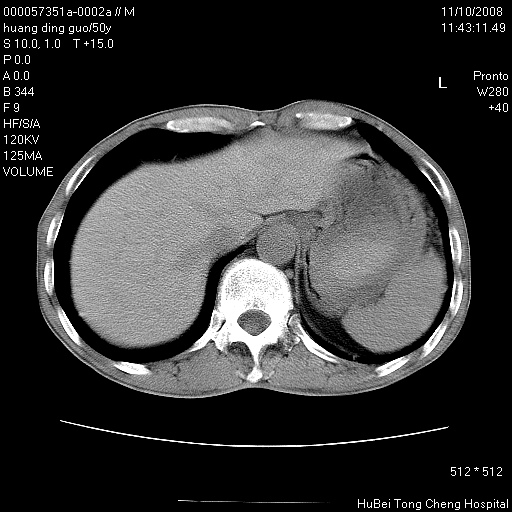

患者 男,50岁。左侧腰背部疼痛3月余,伴消瘦。平素健康,无传染病史。

胸部ct轴位平扫(层厚10mm,螺距1.5,重建间隔10mm),图像如下:

左肺下叶背段有一厚壁空洞,外壁呈锯齿状伴毛刺改变。空洞相邻胸膜有牵拉改变。左肺下叶血管支气管束不规则增粗,小叶间隔增厚。胸椎骨质破坏。考虑左肺下叶周围型肺癌伴左肺下叶癌性淋巴管炎、胸椎转移。

左肺下叶背段有一厚壁空洞,外壁呈锯齿状伴毛刺改变。空洞相邻胸膜有牵拉改变。左肺下叶血管支气管束不规则增粗,小叶间隔增厚。胸椎骨质破坏。考虑左肺下叶周围型肺癌伴阻塞性肺炎、胸椎转移。其他待排

左肺下叶背段有一厚壁空洞,内壁不规则,外壁呈锯齿状伴毛刺改变。空洞相邻胸膜有牵拉改变。周围呈絮状炎性改变,左肺下叶血管支气管束不规则增粗,小叶间隔增厚。胸椎骨质破坏。考虑左肺下叶周围型肺癌伴左肺下叶阻塞性肺炎、胸椎转移。